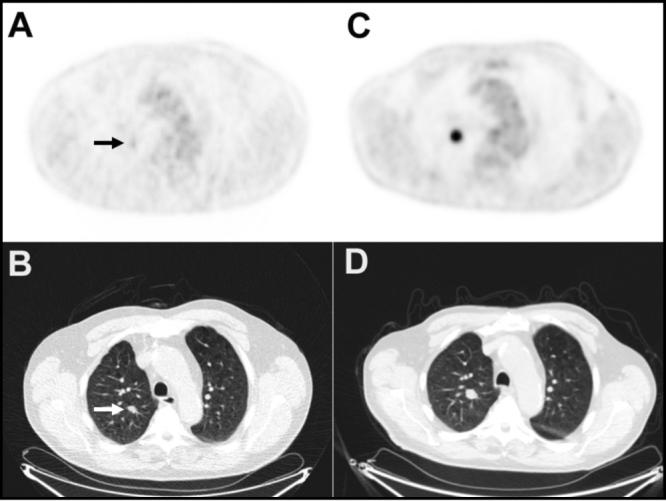

Imaging scans showing a lung nodule in panels A and B that enlarged over 11 months (panels C and D) and later confirmed as lung cancer via biopsy.

Imaging scans identified a lung nodule (panels A and B) which, over the course of 11 months progressed (panels C and D) and, following a biopsy, was confirmed as lung cancer.

Credit: Radiol Case Rep 2013. doi: 10.2484/rcr.v8i3.872. CC BY 4.0.